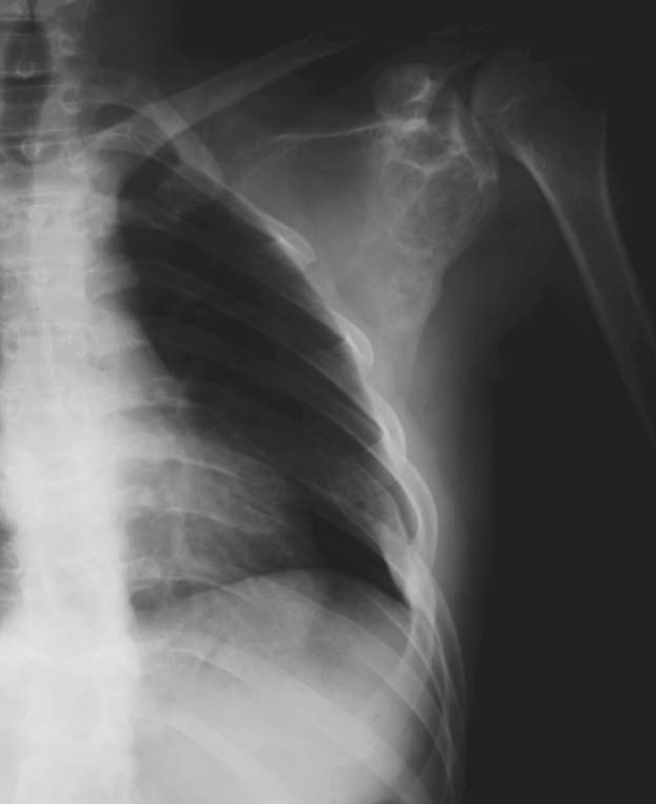

Figure1